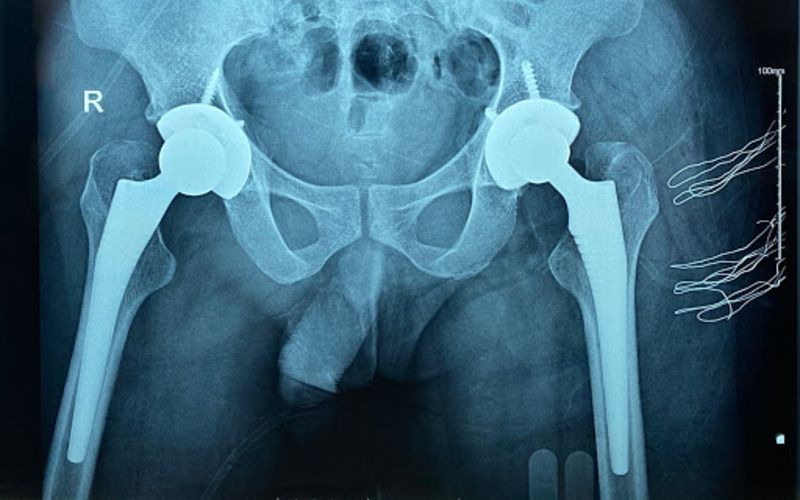

Thăm khám và điều trị y tế

Trong trường hợp đau kéo dài, bác sĩ có thể chỉ định thuốc giảm đau, kháng viêm, vật lý trị liệu hoặc các biện pháp can thiệp chuyên sâu hơn tùy mức độ tổn thương.